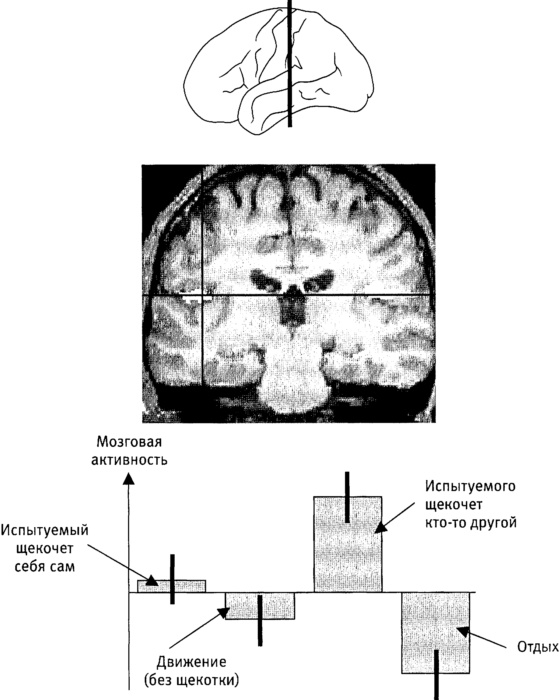

Рис. 4.7. Реакция мозга на щекотку.

Срез через центральную часть мозга, на котором показана область, реагирующая на прикосновение (вторичная соматосенсорная кора). Активность в этом участке мозга выше, когда нас щекочет кто-то другой, чем когда мы пытаемся щекотать себя сами, несмотря на то что сами прикосновения могут быть совершенно одинаковыми. Черные вертикальные отрезки ("усы") показывают степень изменчивости полученных результатов. К диаграммам без "усов" нужно относиться настороженно.